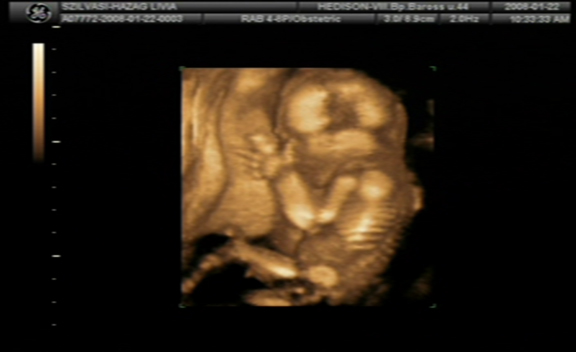

Pannaanya: tök jók a 4D-s képek! Siófok-Sóstó? Na az tőlünk kb. 7 km, ha olvasod és van kedved, akár össze is futhatnánk